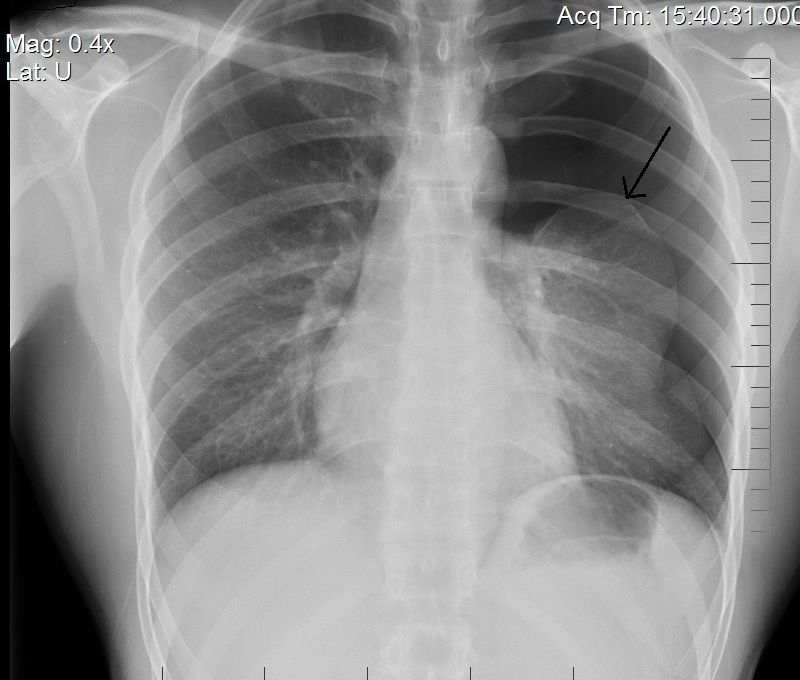

Pneumothorax Pulmonary Disorders Merck Manuals Professional Edition How To Treat A Pneumothorax In The Field Symptoms of pneumothorax include shortness of breath, chest pain on one side and experiencing pain when breathing. Individuals with a pneumothorax and who are in extremis or may decompensate. It may include observation with supplemental oxygen therapy, the use of an ambulatory device (where available),. Pneumothorax in adults can be treated by tube thoracostomy or surgically. The principles of treatment. How To Treat A Pneumothorax In The Field.